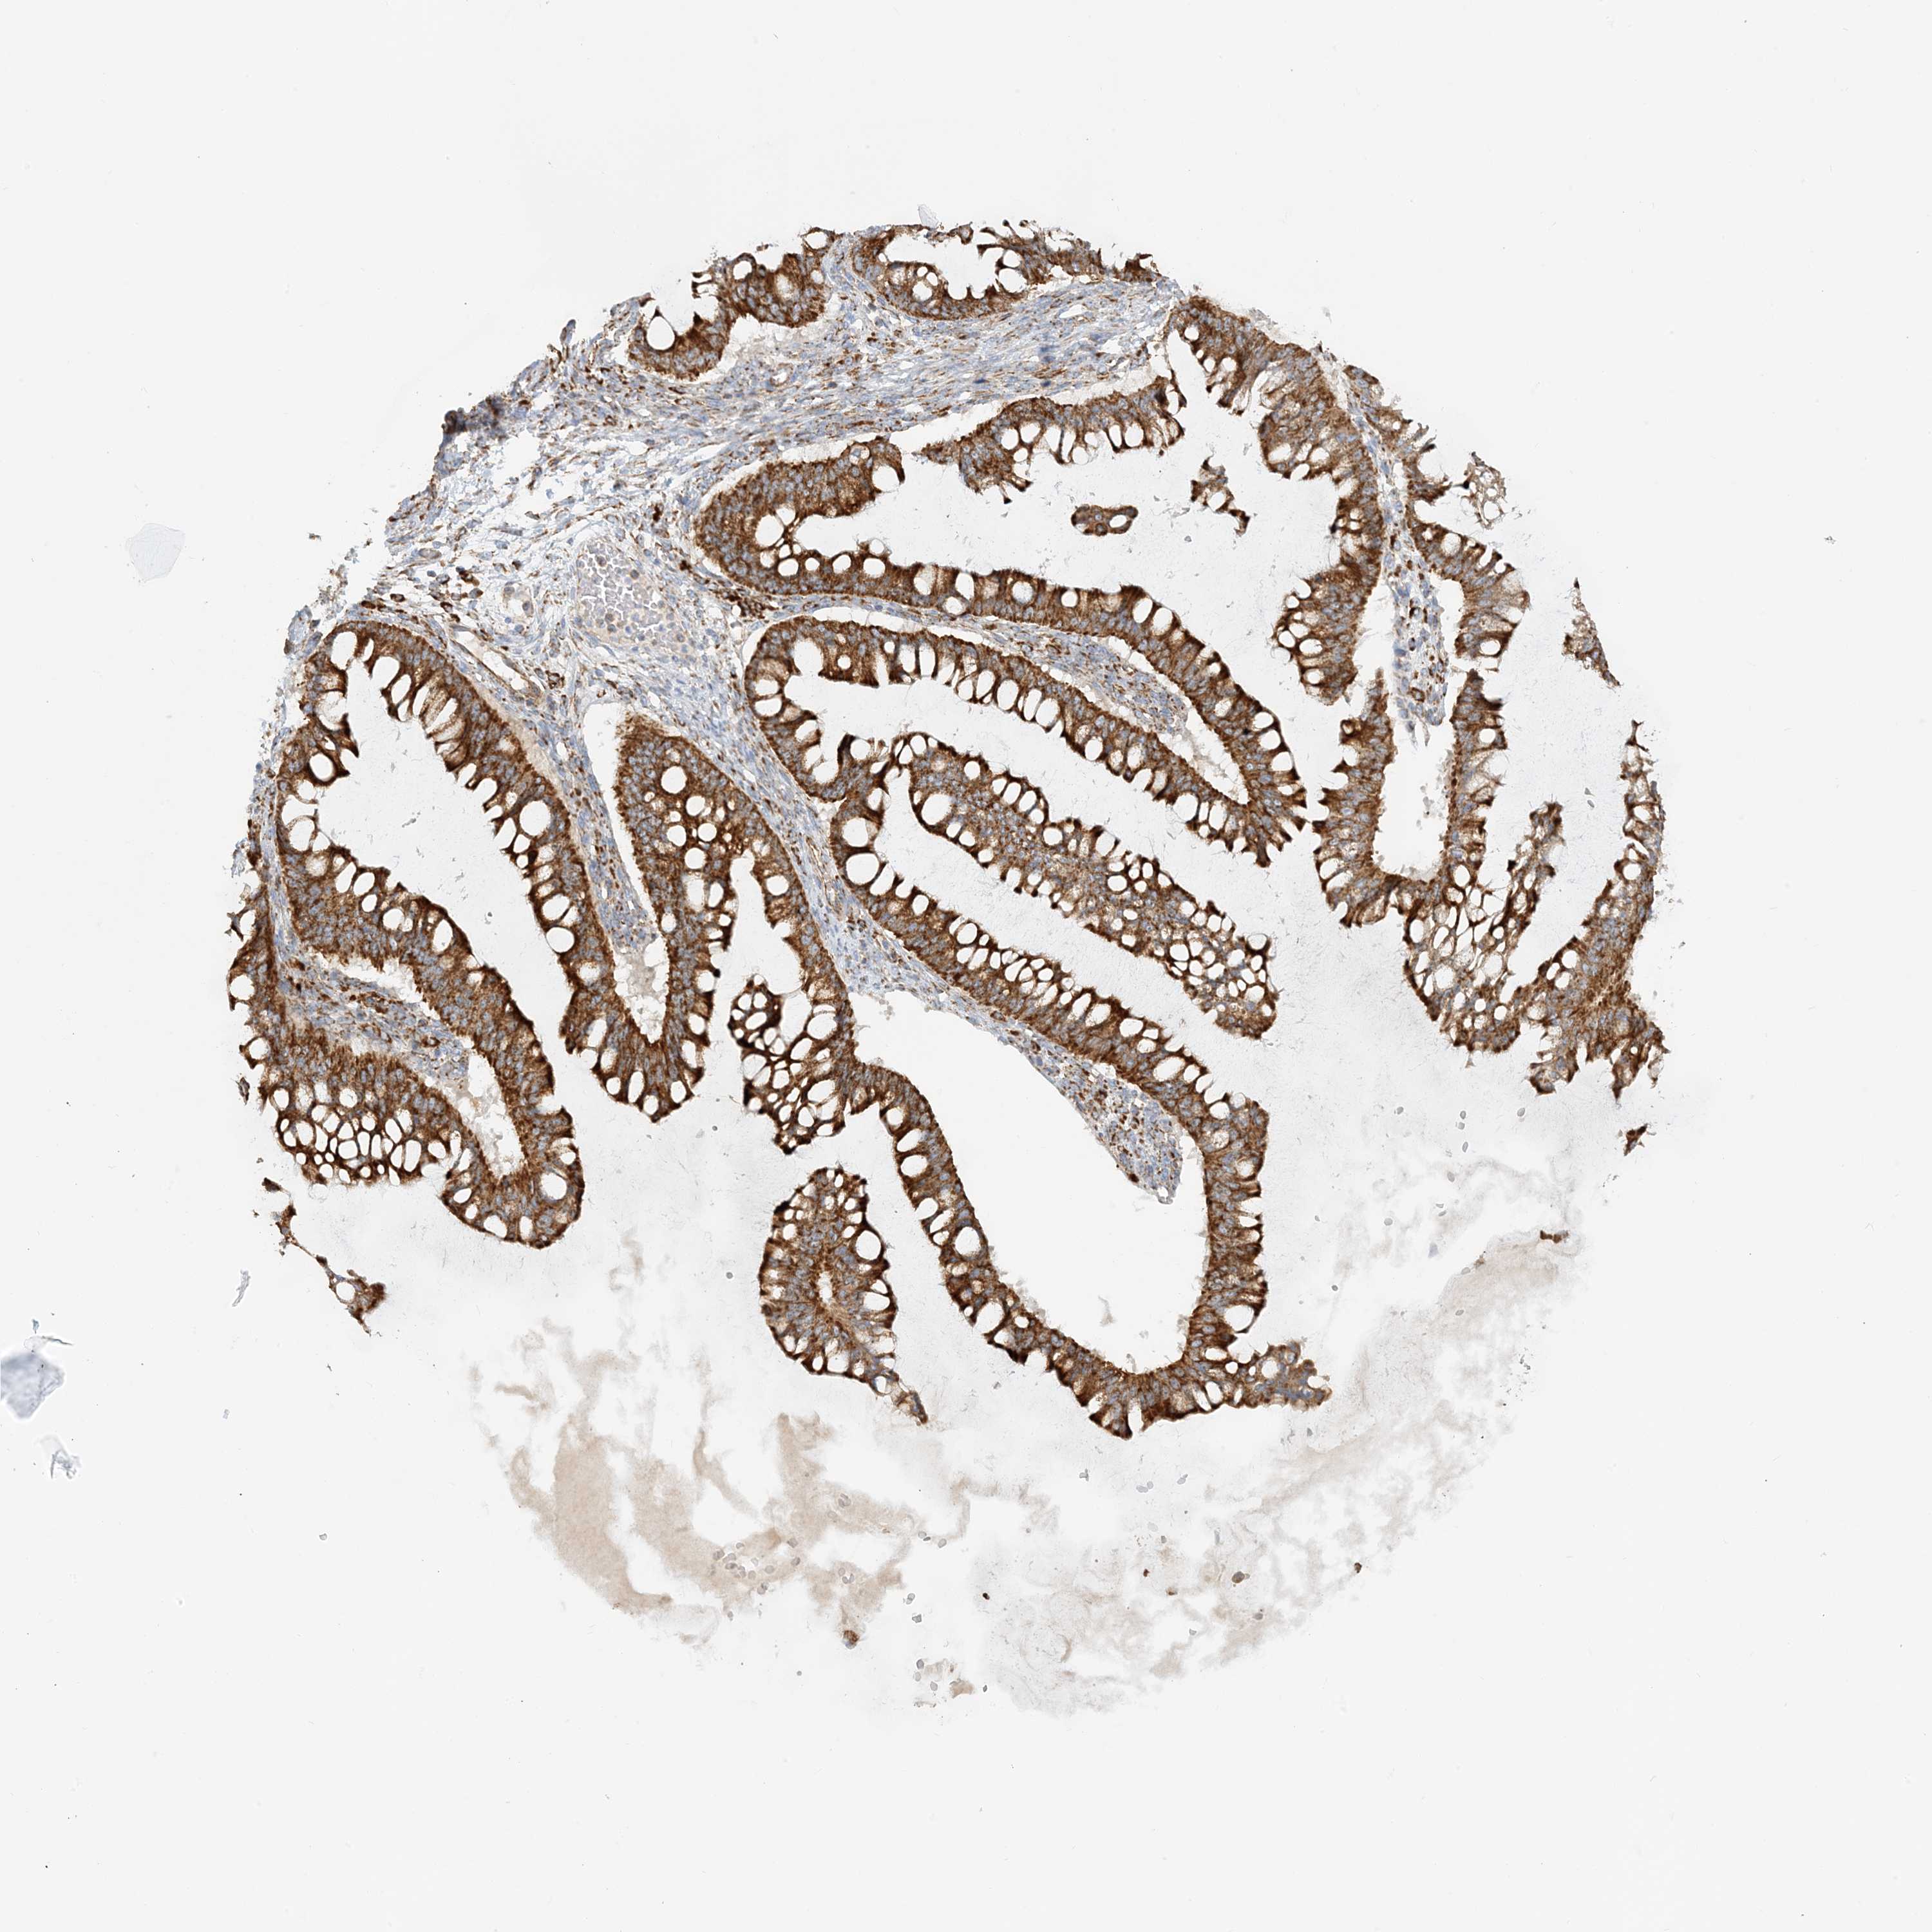

OVARIAN CANCER - Protein expressioni

A mouse-over function shows sample information and annotation data. Click on an image to view it in a full screen mode. Samples can be filtered based on level of antibody staining by selecting one or several of the following categories: high, medium, low and not detected. The assay and annotation is described here.

Note that samples used for immunohistochemistry by the Human Protein Atlas do not correspond to samples in the TCGA dataset.

Antibody stainingi

Antibody staining in the annotated cell types in the current human tissue is reported as not detected, low, medium, or high, based on conventional immunohistochemistry profiling in selected tissues. This score is based on the combination of the staining intensity and fraction of stained cells.

Each image is clickable and will lead to virtual microscopy that enables deeper exploration of all samples and also displays staining intensity scores, fraction scores and subcellular localization as well as patient and tissue information for each sample.

Antibody HPA031966

Staining

High

Medium

Low

Not detected

Intensity

Strong

Moderate

Weak

Negative

Quantity

>75%

75%-25%

<25%

None

Location

Nuclear

Cytoplasmic/membranous

Cytoplasmic/membranous,nuclear

Cystadenocarcinoma, serous, NOS

Carcinoma, endometroid

Cystadenocarcinoma, mucinous, NOS

Carcinoma, NOS